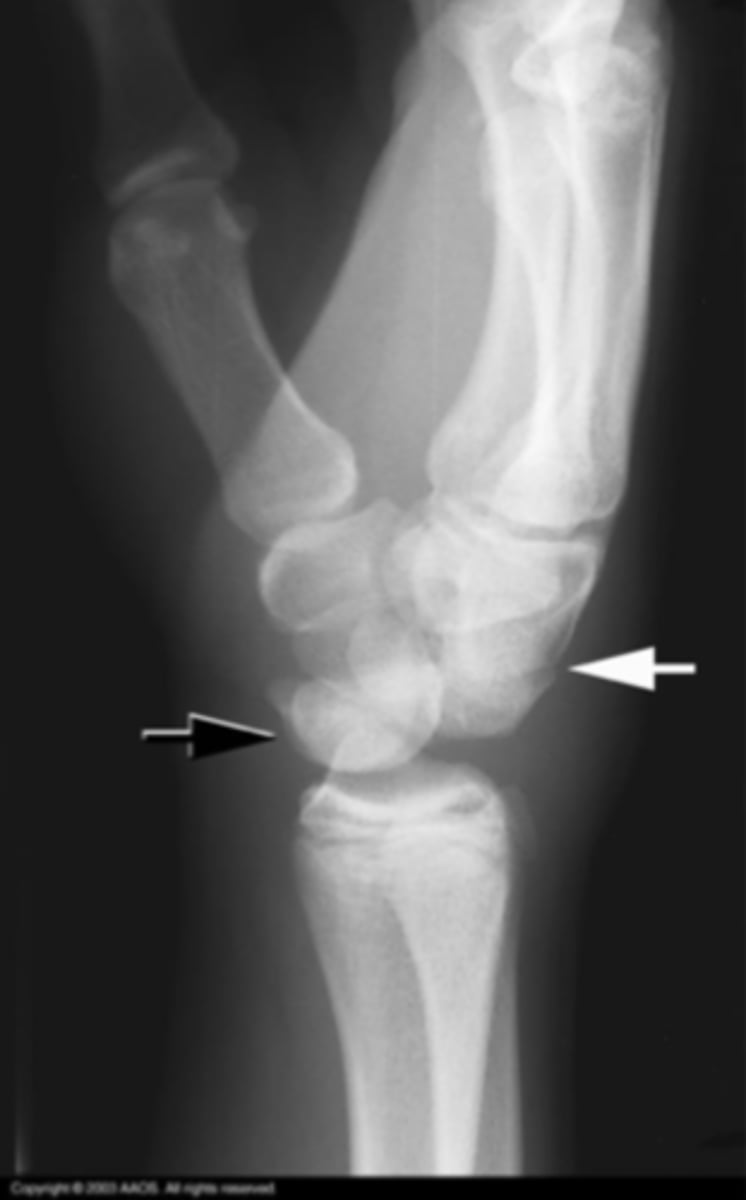

Perilunate instability

What is the issue?